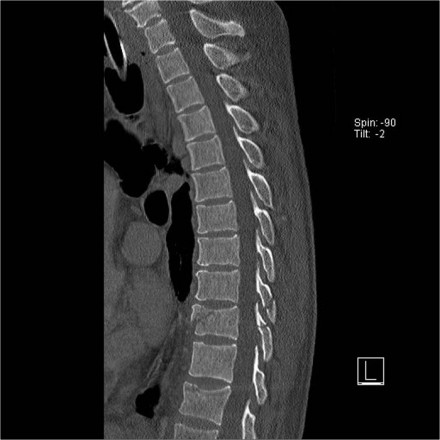

The images are of a patient with a typical bamboo spine as a result of ankylosing spondylitis.

After a fall on his back no fracture was seen on the x-rays.

However the CT shows a thin fracture line through the anterior side of the vertebral body and also through the spinous process.

Continue with the MR-images.